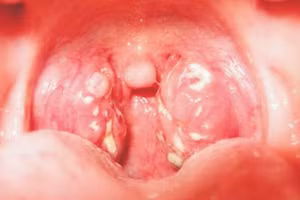

GD&TĐ - Bạch hầu là bệnh truyền nhiễm, dễ lây lan. Ca mắc bệnh hầu biến chứng nặng dẫn đến tử vong gần đây là bé trai 12 tuổi tại tỉnh Kon Tum, một lần nữa nhắc mỗi người cẩn trọng hơn với căn bệnh nguy hiểm này.